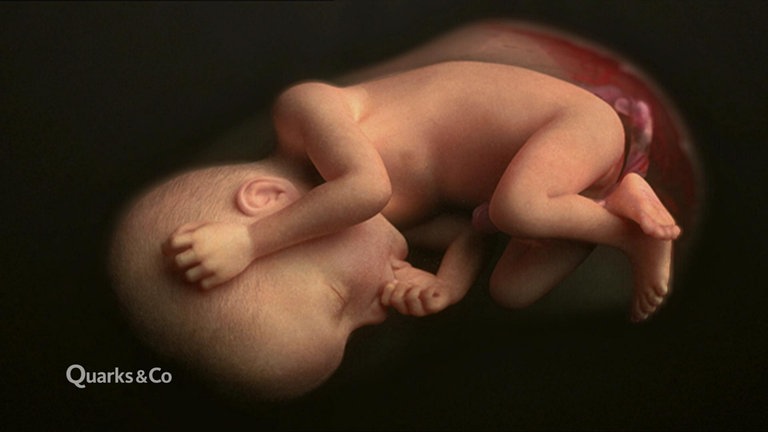

Wie finden sich Spermium und Eizelle? Wann werden im Embryo welche Organe angelegt? Wie verändert sich der Fötus im Verlauf der neunmonatigen Schwangerschaft? Dieser Film porträtiert die Entstehung menschlichen Lebens von der Befruchtung bis zur Geburt.

Wir begleiten die schwangere Sabrina und ihre kleine Tochter Ronja auf ihrem Weg zu Ultraschalluntersuchungen, Schwangerschaftsgymnastik. Mit Sabrina gehen wir dann in den Kreißsaal. Aufwändige Computer-Animationen zeigen die Anatomie der Geschlechtsorgane, illustrieren die Arbeitsweise von Nabelschnur und Plazenta und veranschaulichen ausgewählte Entwicklungsschritte des Kindes im Mutterleib.